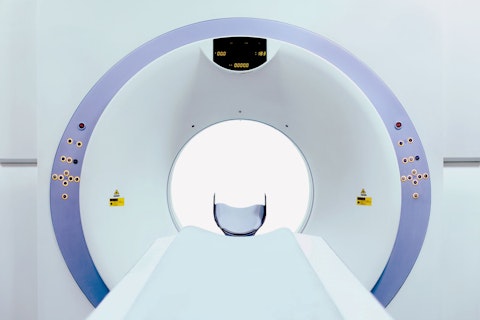

Treffen Sie uns auf der MEDICA 2023

Sie möchten Ihr Medizinprodukt nach MDR prüfen und zertifizieren lassen und dabei nicht durch lange Wartezeiten ausgebremst werden oder erwägen als Medizinproduktehersteller einen Wechsel Ihrer Benannten Stelle?

Die SGS auf der MEDICA 2022 in Düsseldorf (14. - 17. November)

Die Experten der SGS – Weltmarktführer im Bereich Testen, Prüfen und Zertifizieren – informieren Sie auf der weltweit größten Veranstaltung für die Medizinbranche, wie Sie Ihre Medizinprodukte international erfolgreich in Verkehr bringen und welche Normen und Verordnungen Sie einhalten müssen.